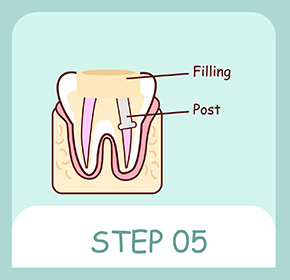

被せ物が安定するように歯を削った部分を埋め、歯の欠損が大きい場合には歯の土台(コア)を造成します。

土台と適合する被せ物を作製します。被せ物を装着し、かみ合わせの確認をして治療終了です。